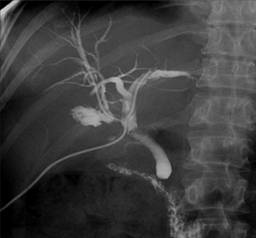

La elección del tratamiento adecuado para las IBDI es crucial, ya que puede evitar estas complicaciones graves y mejorar la calidad de vida de los pacientes. Por lo tanto, la cuestión sobre el tipo de tratamiento para los pacientes con IBDI sigue siendo un tema de debate. Inicialmente, se recomienda el tratamiento endoscópico en pacientes con IBDI. Cuando las técnicas endoscópicas no son efectivas, se realizan diferentes reconstrucciones quirúrgicas. El objetivo del tratamiento quirúrgico es la reconstrucción para permitir un buen flujo biliar hacia el tracto alimentario. Para lograr este objetivo, se utilizan muchas técnicas. Existen opiniones contradictorias sobre las diferentes reconstrucciones quirúrgicas en la literatura.

El tratamiento inicial recomendado para las IBDI suele ser endoscópico. Las técnicas endoscópicas son menos invasivas y se realizan a través de un endoscopio, un tubo delgado con una cámara y herramientas pequeñas, lo que permite a los médicos visualizar y tratar el área afectada sin necesidad de una cirugía mayor. Estos métodos pueden ser efectivos para resolver el problema en algunos casos, especialmente cuando la lesión es relativamente menor o localizada. La ventaja de los tratamientos endoscópicos es que suelen implicar menos riesgos y una recuperación más rápida en comparación con las intervenciones quirúrgicas más extensas.

Sin embargo, cuando las técnicas endoscópicas no logran el resultado deseado, se deben considerar opciones quirúrgicas más complejas. La cirugía en estos casos busca reconstruir el conducto biliar para restaurar el flujo normal de bilis hacia el tracto digestivo. Esta reconstrucción es esencial para asegurar que la bilis pueda fluir adecuadamente, evitando así la acumulación y los problemas asociados que pueden surgir de un flujo biliar bloqueado o alterado.